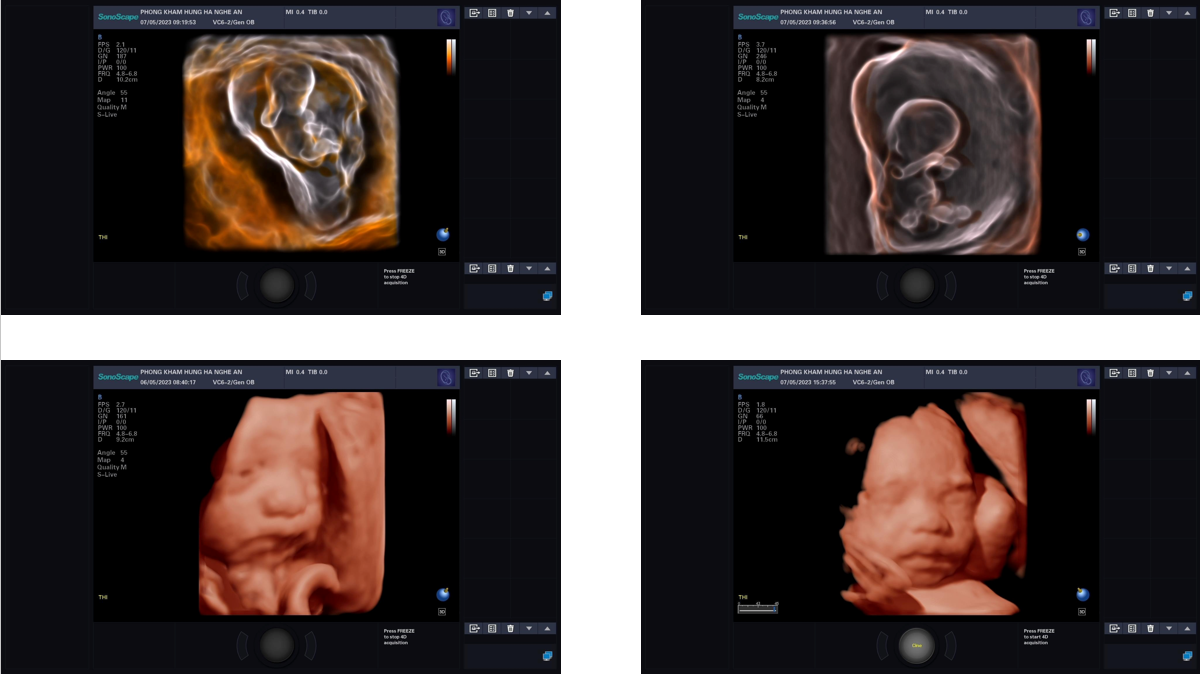

- S- Silhouttle: làm mờ các màng cúng như thành bụng mẹ, túi ối, màng da và lớp nỏ não trẻ, phát hiện hiện tượng não úng thủy từ giai đoạn thai sớm. (chỉ các dòng máy cao cấp nhất cuát Phillip, GE mới có).

-S-depth: xác định vị trí thai nhi trong bụng mẹ với trường hợp sản phụ đa thai.

- Skeleton: siêu âm xương thai nhi, phát hiện dị tật xương

- Công nghệ like mirror, phát hiện bệnh não úng thuỷ sớm ở thai nhi từ giai đoạn thai sớm (dứoi 3 tháng tuổi)

Hình ảnh thực tế trên máy siêu âm 5D SonoScape P25